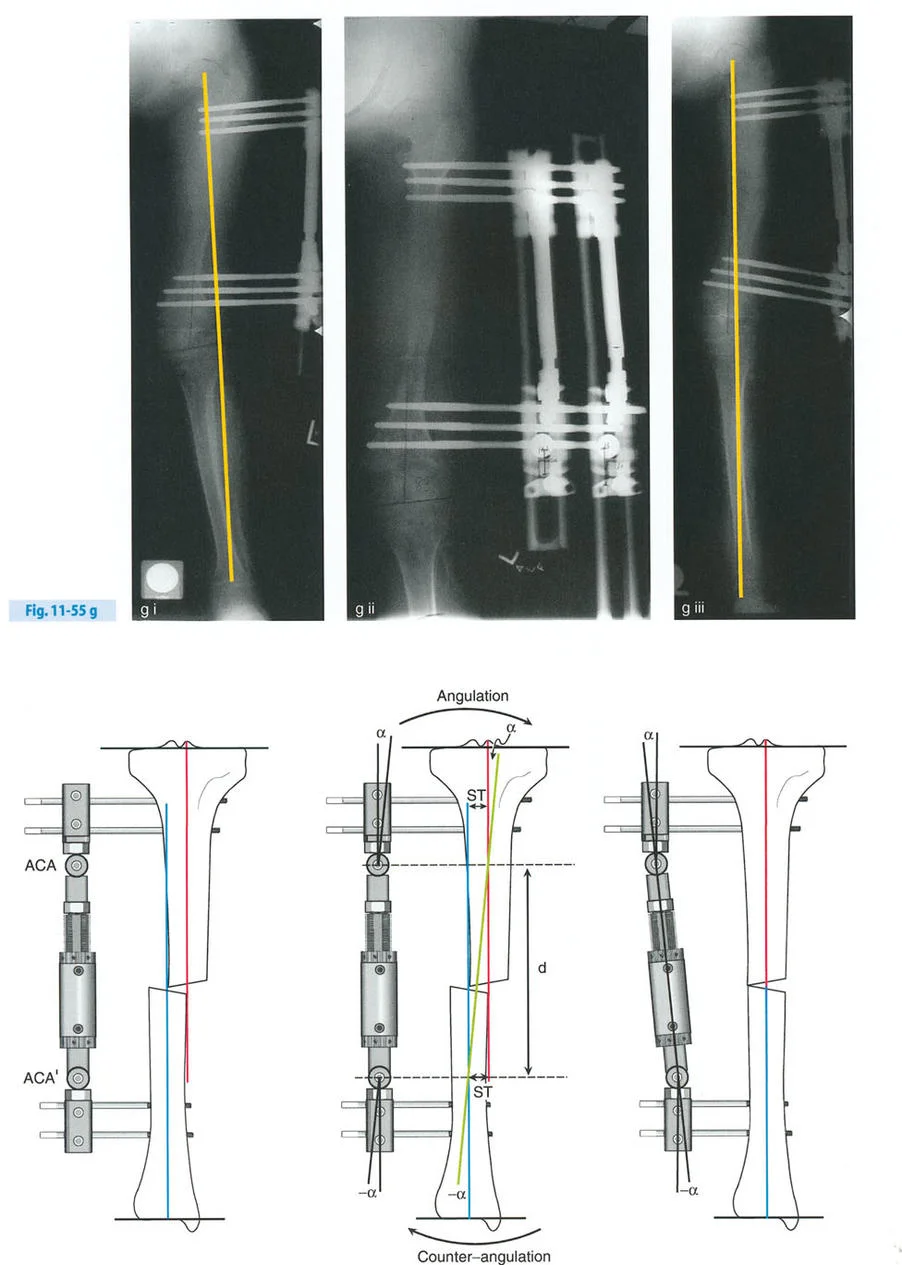

- قاعدة قطع العظم 1: عندما يمر قطع العظم ومحور تصحيح الانحراف (ACA) كلاهما عبر مركز دوران الانحراف (CORA)، فإن نهايات العظم ستنحرف دون ترجمة (انزياح). يتم استعادة المحور الميكانيكي، وتظل نهايات العظم متقاربة تمامًا، مما يخلق تصحيحًا كلاسيكيًا "إسفينيًا مفتوحًا" أو "إسفينيًا مغلقًا".

- قاعدة قطع العظم 2: عندما يمر محور تصحيح الانحراف (ACA) عبر مركز دوران الانحراف (CORA)، ولكن يتم إجراء قطع العظم على مستوى مختلف (غالبًا بسبب ضعف جودة العظم عند CORA أو مشاكل في الجلد)، فإن نهايات العظم ستنحرف وتخضع لترجمة محسوبة ومقصودة لإعادة محاذاة المحور الميكانيكي.

- قاعدة قطع العظم 3: (للاكمال) عندما يمر قطع العظم عبر مركز دوران الانحراف (CORA)، ولكن يتم وضع محور تصحيح الانحراف (ACA) خارج CORA، سيتم إنشاء تشوه ترجمة جديد، وهو خطأ شائع في وضع المفصلات غير المخطط له جيدًا.

في المنشآت القريبة من المفصل، غالبًا ما نعتمد على قاعدة قطع العظم 2. نظرًا لأنه لا يمكننا قطع العظم بأمان عند خط المفصل تمامًا (مركز دوران الانحراف CORA)، فإننا نقطع العظم في مستوى أدنى في منطقة الميتافيسيس. بعد تحقيق التصحيح الزاوي عبر المفصلات (محور تصحيح الانحراف ACA)، يتم إعادة محاذاة خطوط المحور الميكانيكي بشكل مثالي، ولكن نهايات العظم في موقع قطع العظم تتحرك بالنسبة لبعضها البعض.